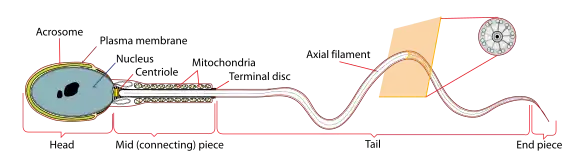

A mature human Spermatozoon | |

During spermiogenesis, the spermatids begin to form a tail by growing microtubules on one of the centrioles, which turns into basal body. These microtubules form an axoneme. Later the centriole is modified in the process of centrosome reduction.[16] The anterior part of the tail (called midpiece) thickens because mitochondria are arranged around the axoneme to ensure energy supply. Spermatid DNA also undergoes packaging, becoming highly condensed. The DNA is packaged firstly with specific nuclear basic proteins, which are subsequently replaced with protamines during spermatid elongation. The resultant tightly packed chromatin is transcriptionally inactive. The Golgi apparatus surrounds the now condensed nucleus, becoming the acrosome.

Maturation then takes place under the influence of testosterone, which removes the remaining unnecessary cytoplasm and organelles. The excess cytoplasm, known as residual bodies, is phagocytosed by surrounding Sertoli cells in the testes. The resulting spermatozoa are now mature but lack motility. The mature spermatozoa are released from the protective Sertoli cells into the lumen of the seminiferous tubule in a process called spermiation.

The non-motile spermatozoa are transported to the epididymis in testicular fluid secreted by the Sertoli cells with the aid of peristaltic contraction. While in the epididymis the spermatozoa gain motility and become capable of fertilization. However, transport of the mature spermatozoa through the remainder of the male reproductive system is achieved via muscle contraction rather than the spermatozoon's recently acquired motility.